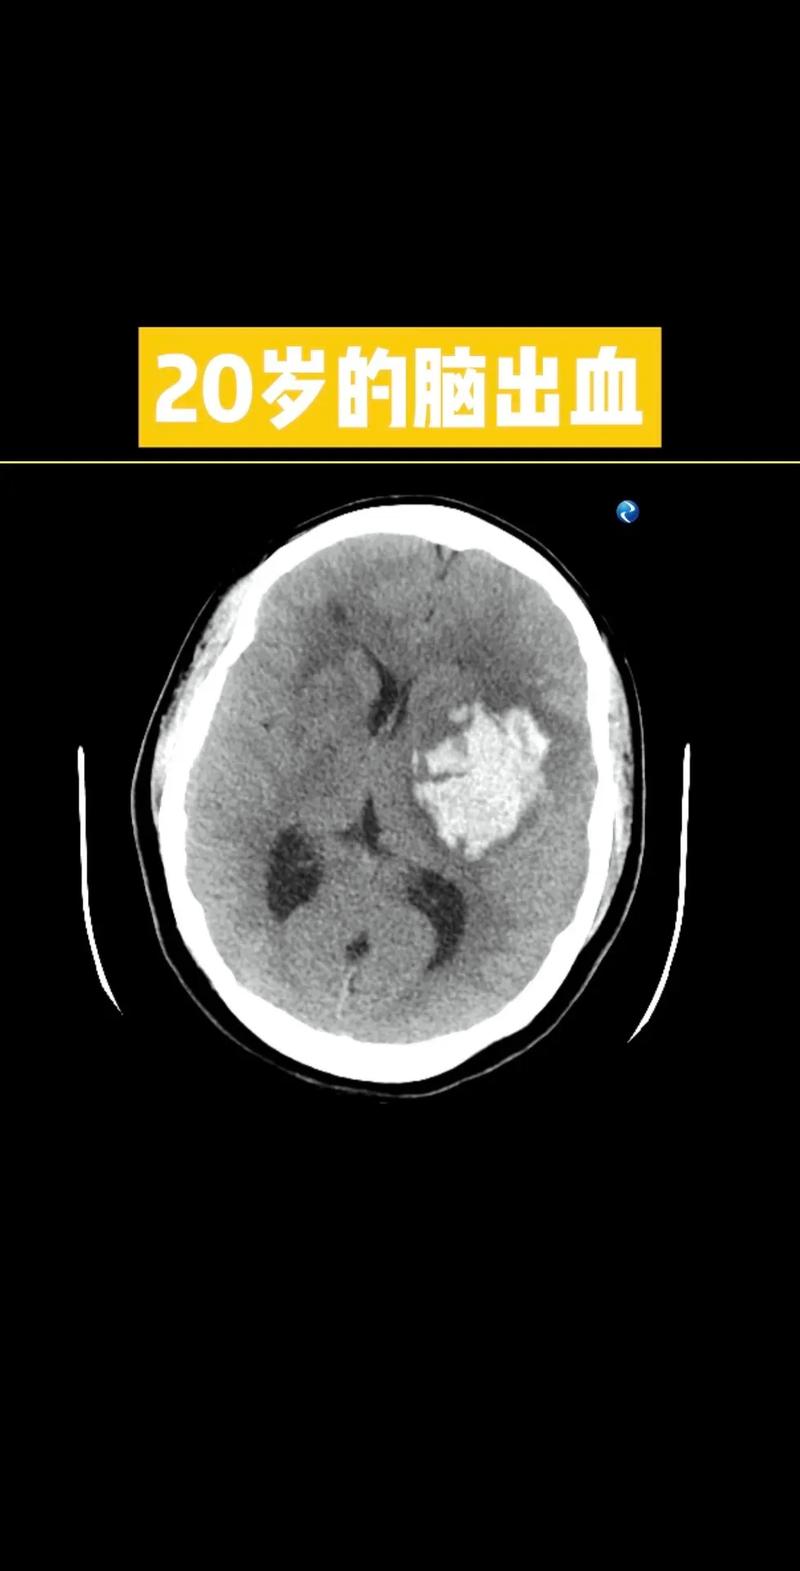

这种情况的严重性取决于几个关键因素,需要由医生通过影像学检查(主要是头颅CT)来判断:

- 出血量:出血量越大,对周围脑组织的压迫越严重,病情就越凶险。

- 出血部位:出血是否在关键功能区(如脑干、基底节区等),这直接关系到患者的生命体征和神经功能缺损程度。

- 是否形成血肿:是仅仅有点渗血(点状出血),还是形成了明显的、占位效应的血肿(团块状出血)。

- 占位效应:血肿是否会压迫周围的脑组织,导致中线移位,这是危及生命的紧急情况。